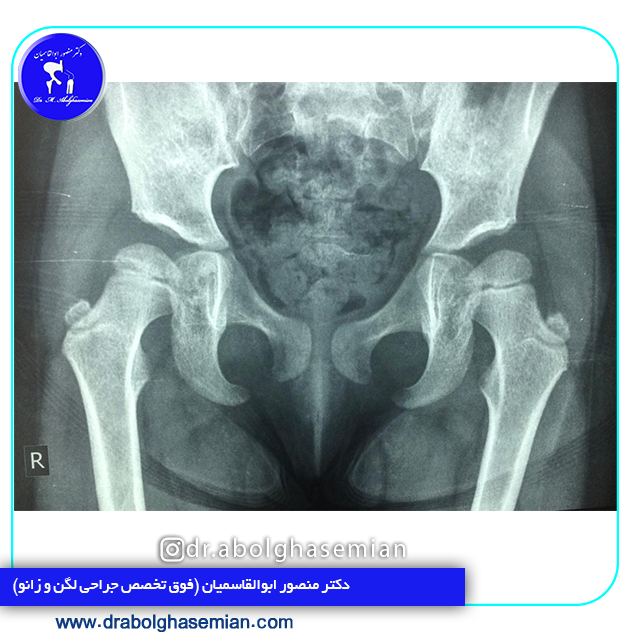

غربالگری سال های اول تولد یکی از مهم ترین اقدامات می باشد. منظور از غربالگری، معاینه فیزیکی پاها و لگن می باشد. تست هایی وجود دارند که قبل از سه ماهگی انجام می شوند. اولتراسوند برای نوزادان تا چهار ماه و اشعه ایکس برای شیرخواران بالای چهار ماه به تشخیص این اختلال کمک خواهد کرد.

نوزادانی که بیشتر در معرض خطر ابتلا به DDH قرار دارند اغلب با استفاده از سونوگرافی آزمایش می شوند که می تواند تصاویری از استخوان های ران را نمایان کند. برای نوزادان بزرگتر و کودکان، از اشعه ایکس برای تهیه تصاویر مفصلی استفاده می شود.